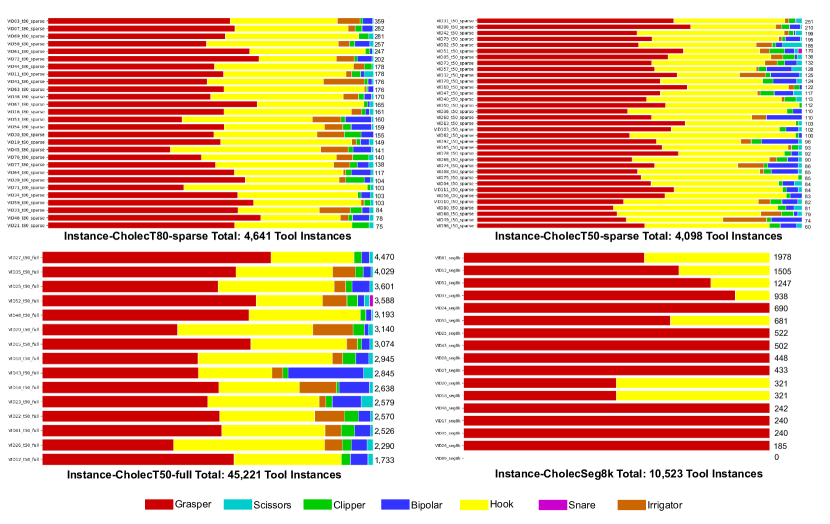

Partition and Sequence Analysis

Table 2 provides a summary of the number of sequences, number of frames and amount of annotated tools in each of the dataset partitions. Figure 8 provides an analysis of tool instances across different sequences and their partitions. Instance-CholecT50-full has the highest number of tool instances, whereas Instance-CholecT50-sparse has the fewest. This figure highlights the imbalance between densely and sparsely annotated sequences and the presence of a sequence with no tools in Instance-CholecSeg8k.

| Inst-CholecSeg8k | Inst-CholecT50-sparse | Inst-CholecT50-full | Inst-Cholec80-sparse | Total | |

|---|---|---|---|---|---|

| No of seq | 17(10 shared) | 35 | 15(10 shared) | 28 | 85 |

| No of frames | 8,080 | 2,681 | 28,317 | 2,855 | 41,933 |

| No of tools | 10,523 | 4,098 | 45,221 | 4,641 | 64,483 |